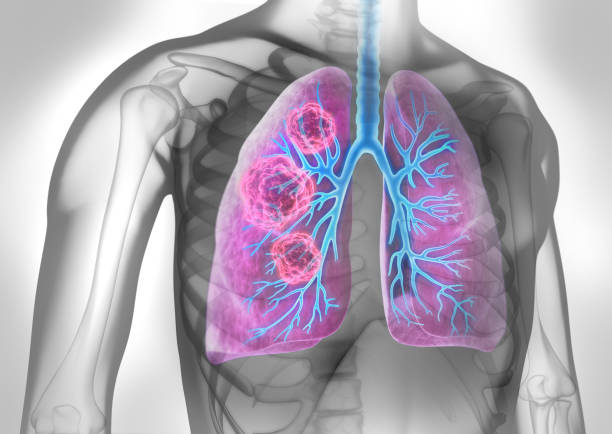

폐암 원인

폐암 원인은 다양하지만 유전적 요인, 환경적 요인, 흡연 등이 있는 것으로 알려져 있으며 가족력이 특히 중요해 가족력이 있는 경우 꾸준한 관리가 중요합니다. 또한, 폐암의 대표적인 병인으로서 흡연은 직간접적인 영향이 강하여 폐암의 병인과 떼려야 뗄 수 없는 중요한 것으로 여겨집니다.

폐암 예방

폐암 예방은 궁극적으로 폐암의 원인을 차단하는 것이며, 흡연자라면 기본적으로 금연을 해야 합니다. 아울러한 최근 여성의 폐암 발병률이 증가하고 있는데 아무래도 가스레인지를 통해 폐에 유해 물질이 들어가는 경우가 많기 때문입니다. 따라서 가족력이 있는 사람은 남녀를 가리지 말고 정기적으로 건강 검진을 받아야 하며 가족력이 없다 하더라도 주의를 기울이고 정기적인 건강 검진을 받는 것이 좋습니다.